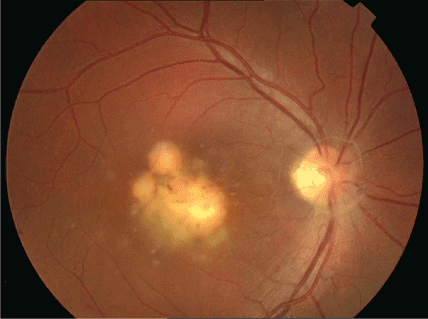

Toxoplasmosis Gondii Chorioretinitis

Toxoplasmic chorioretinitis - Wikipedia A typical chorioretinitis by toxoplasma Ocular Toxoplasmosis: Overview, Pathogenesis, Congenital Versus ... Toxoplasmosis - EyeWiki Fundus photograph of left eye showing active chorioretinitis of ... Toxoplasmosis Gondii Chorioretinitis